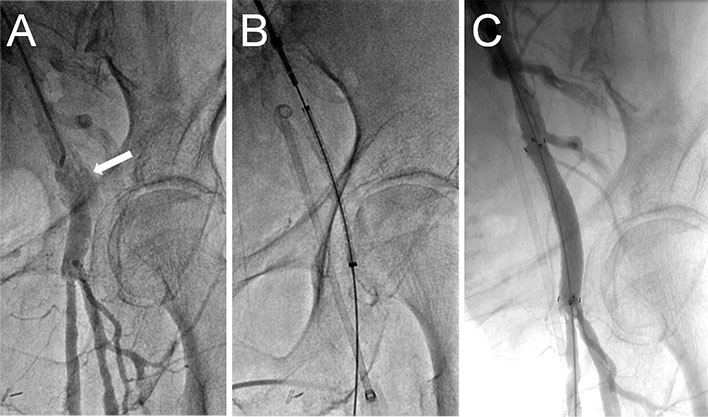

Figure 1

Annulus sizing using TEE and CT angiography. TEE measured an annulus of 2.1 cm suggesting a 23 mm Edwards Sapien or a 26 mm Medtronic CoreValve (A). CT angiography measured an area of 481 mm2 (C) and a mean diameter of 24 mm (B) suggesting a 26 mm Edwards Sapien or a 29 mm Medtronic CoreValve valve with ~10% oversizing. A 26 mm Edwards Sapien valve was implanted with trace paravalvular leak (D).